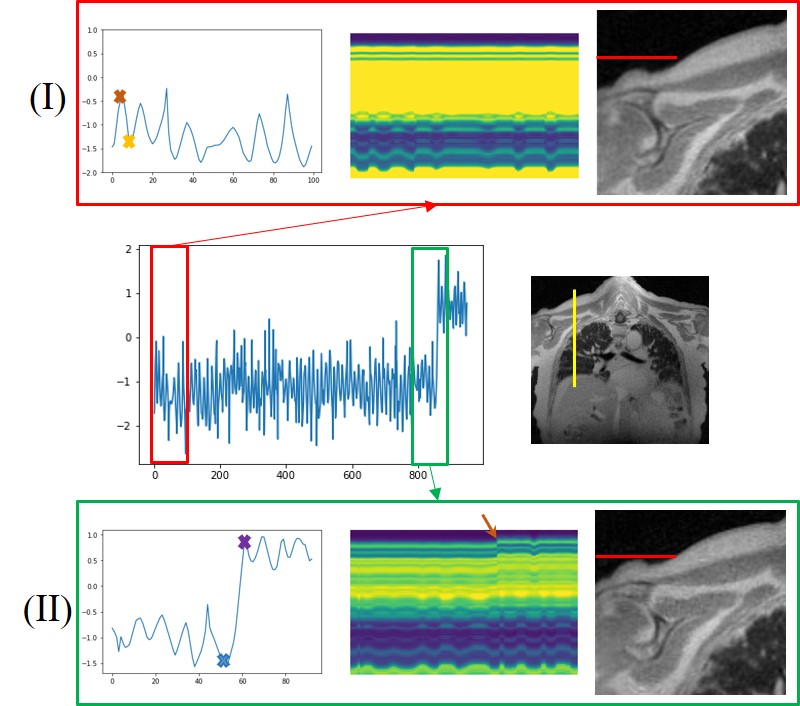

In Fig. 4, we show the learned latent vectors, time profiles, and example estimated deformation maps and corresponding time profiles from the pre-contrast dataset from the healthy subject. We show the estimated latent vectors from the first 200 frames in (a). We also show the time profile of the reconstructed images in (b) and the time profile of the deformation maps in (c), corresponding to the blue lines in the images. From the two profiles, we see that the motion patterns coincide with the learned latent vectors. In (d) we show the estimated deformation maps from two time points, indicated by red and green dots in (a), corresponding to the inhalation phase and the exhalation phase. The results show that the latent vectors closely capture the dynamics of the motion.

Refer to caption

Figure 4: Illustration of the learned quantities from the pre-contrast healthy volunteer. In (a), we show the estimated latent vectors corresponding to the first 200 frames, while (b) and (c) show the time profile of the reconstructed image volumes and the deformation maps, respectively. From the three figures on the left, we see that the motion patterns in the time profiles closely match the learned latent vectors. In (d), we show the deformation maps in the three directions, corresponding to the time frames marked by red and green cross marks in the latent vectors in (a).

(a) Latent vectors and motion detection

(b) Exemplar deformation maps

Figure 7: Impact of bulk motion. (a) shows the latent vectors estimated from the proposed scheme, which are zoomed to regions without bulk motion (I) and regions with bulk motion (II), captured by the discontinuity in the latent vectors. We plot the time profiles at the position marked by the yellow line in the image shown in the middle row. From the plots of the time profiles, we see the subject moved his shoulder during the scan, evidenced by the rightmost reconstructed frame in (I) and (II), respectively; the red lines are in the same location, indicating motion in the shoulder. We also show show four exemplar deformation maps corresponding to four time points marked in (I) and (II). We note that the deformation maps with yellow and blue borders corresponding to the local minima of the latent vectors are similar. By contrast, the local maxima of the map with the purple border shows significant deviation from the one with the red border.

4.4.1 Adult study:

In the post-contrast dataset acquired from a diseased subject, we detected one bulk motion, which is shown in Fig. 7. In Fig. 7 (a), we show the latent vectors that are learned using MoCo-SToRM. As we mentioned before, the sudden jump in the latent vectors indicates the bulk motion. We highlight two time regions, one without bulk motion (red box) and one with bulk motion (green box). We also show the time profiles of the yellow line indicated in Fig. 7 (a). From the plots of the time profiles, we see that when the latent vectors have no sudden jump, then no bulk motion can be seen. However, when sudden jump happens in the latent vectors, we clearly see a bulk motion event from the time profile. In (I) of Fig. 7 (a), we zoomed the reconstructed image corresponding to the yellow cross shown in the latent vectors, and in (II) of Fig. 7 (a), we zoomed the reconstructed image corresponding to the purple cross shown in the latent vectors. From the red line marker, we can see that the subject moved the shoulder during the scan.

In Fig. 7 (b), we also show the deformation maps estimated by the proposed scheme at four different time points indicated by the brown, yellow, blue, and purple crosses in Fig. 7 (a). From the red ellipses in the images, we see that the subject moved the shoulder during the scan. The deformation map will be very different from the deformation maps when there is no bulk motion. In Fig. 5 (b), we compared the reconstructions from the proposed scheme and the iMoCo and XD-GRASP reconstructions. From the figure, we see that the proposed scheme is able to deal with bulk motion and offer improved reconstructions.